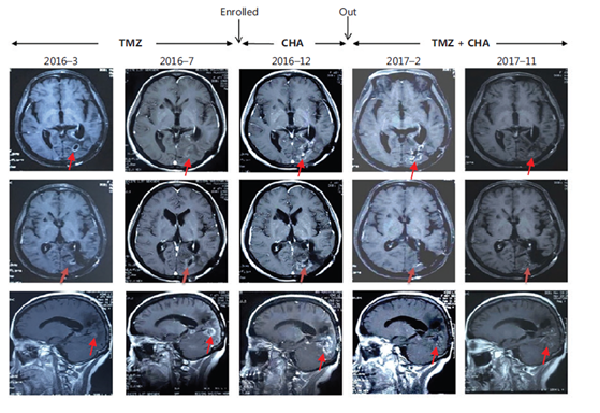

治療惡性腦膠質(zhì)瘤Ⅰ期臨床研究特殊病例分析:注射用綠原酸有效延長(zhǎng)受試者生存期,并能一定程度解除受試者對(duì)替莫唑胺的耐藥現(xiàn)象

受試者入組時(shí)替莫唑胺耐藥且疾病進(jìn)展;

使用注射用綠原酸后病情得到有效控制,出組后再次使用替莫唑胺治療,MRI結(jié)果顯示替莫唑胺再次起效。

患者采用替莫唑胺與注射用綠原酸交替使用、聯(lián)合治療的方案,顱內(nèi)病灶目前已完全消失,從確診至今,生存期已超過(guò)13年。

病例圖片來(lái)源 Kang, Z. , Li, S. , Kang, X. , Deng, J. , Yang, H. , & Cheni, F. , et al. (2023). Phase Ⅰ study of chlorogenic acid injection for recurrent high-grade glioma with long-term follow-up. 癌癥生物學(xué)與醫(yī)學(xué):英文版, 20(6), 465-476.